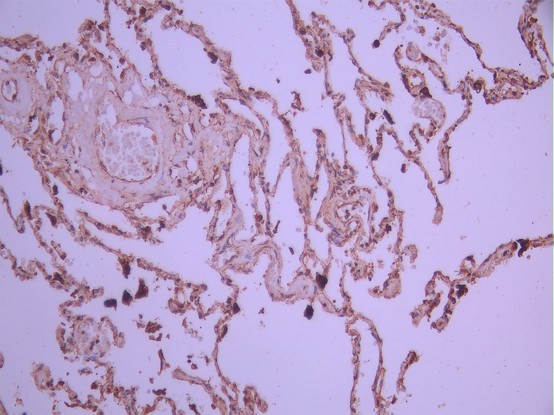

• IHC image of CSB-RA055227A0HU diluted at 1:100 and staining in paraffin-embedded human lung tissue performed on a Leica BondTM system. After dewaxing and hydration, antigen retrieval was mediated by high pressure in a citrate buffer (pH 6.0). Section was blocked with 10% normal goat serum 30min at RT. Then primary antibody (1% BSA) was incubated at 4°C overnight. The primary is detected by a Goat anti-rabbit polymer IgG labeled by HRP and visualized using 0.05% DAB.